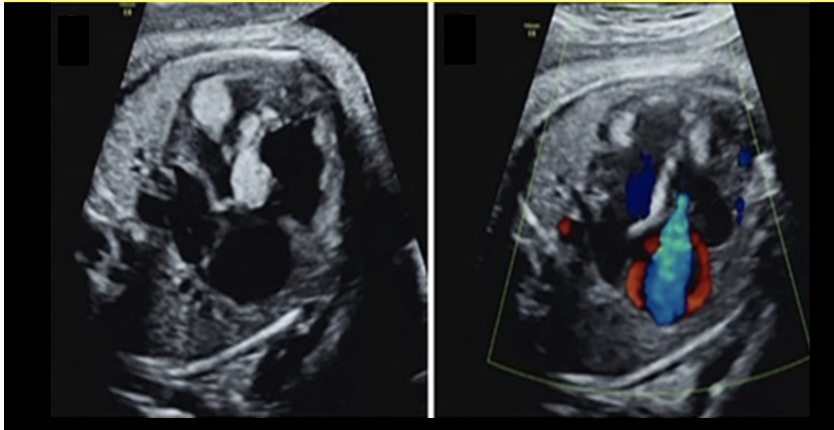

what congenital anomaly is shown

a) renal agenesis

b) duodenal atresia

c) anal atresia

d) posterior urethral valves